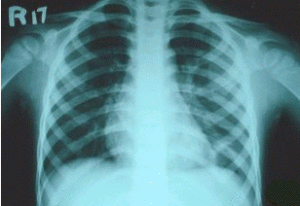

間質性肺炎X線檢查 實驗室檢查:血液檢查:間質性肺病肺泡結構中炎性和免疫細胞異常與肺外其他病變無關聯,許多患者血沉增速,或血液免疫球蛋白增高,與肺纖維化亦無密切關聯。有些患者血清中可查到免疫複合體,是從肺臟產生而溢出的。有一部分患者類風濕因子、抗核抗體陽性,部分患者血清出現抗肺膠原抗體。動脈血氣分析:由於潮氣量減低,呼吸頻率增高,呼吸淺速,肺泡通氣量不足,導致通氣/血流比例降低,發生低氧血症,但動脈血二氧化碳分壓正常。運動後血氧分壓明顯下降。支氣管肺泡灌注檢查:套用纖維支氣管鏡插入左肺舌葉或右肺中葉,以生理鹽水沖入灌洗,獲得支氣管肺泡灌洗液。將灌洗液作細胞學和非細胞成分的測定。本法具有以下優點:①灌洗液的細胞學檢查能真實地反映肺泡炎肺泡結構中的炎性和效應細胞的類型與數目。②各種間質性肺病的診斷與鑑別診斷。非吸菸人灌洗液的細胞總數為(0.2~0.5)×10E4/ml 其中肺泡巨噬細胞占85%~90%,淋巴細胞約占10%,中性粒細胞及嗜酸粒細胞僅占1%以下,細胞總數多由肺泡巨噬細胞的增加而增加,而細胞種類的變化在ILD 時有診斷意義。如過敏性肺泡炎、結節病、慢性鈹肺時淋巴細胞顯示明顯增加。膠原病伴肺間質纖維化時也可見淋巴細胞增加。而細菌性肺炎、氣道感染以及ARDS 時嗜中性粒細胞增加。閉塞性細支氣管炎伴機化性肺炎時可出現淋巴細胞、粒細胞的增加。支氣管肺泡灌洗液的淋巴細胞中T 細胞占70%~80%,B 細胞占10%~20%,而ILD 中的結節病、過敏性肺泡炎、慢性鈹肺則T 細胞增加。一直想用標記T 細胞亞群或T 細胞、B細胞的活化程度解釋ILD 的活動性和預後。僅見結節病時T細胞數及活化T 細胞數的增加與病情的進展情況相關。此外在特發性肺間質纖維化時活化的B 細胞增加則提示病情的進展,淋巴細胞增多則對激素治療效果較好,其預後也較好。

間質性肺炎確診圖 2.肺功能檢查 此項檢查僅是功能的診斷,而非病理診斷,在早期階段,肺功能檢查可以完全正常,當病情進展才可能出現肺功能檢查的異常。ILD 最顯著的肺功能變化為通氣功能的異常和氣體交換功能的降低。通氣功能是以限制性通氣障礙為主、肺活量減少、殘氣量隨病情進展而減少,隨之肺總量也減少。第1s 時間肺活量(FEV1.0)與用力肺活量(FVC)之比即1s 率出現明顯升高,如已達到90%則支持ILD 的診斷。ILD 的早期可有小氣道功能障礙,其V50、V25均降低ILD形成纖維化後而出現V50、V25 增加。ILD 的早期還可以出現氣體交換功能障礙,如彌散功能(DLCO)較早期即有降低,一旦X 線胸片發現間質性改變,DLCO 則已降低50%以下。肺功能改變與肺部病變二者的相關性,在病變輕微者極差,病情嚴重者相關性較好。凡肺功能嚴重損害者,肺部病變肯定嚴重。在肺功能的各項檢測中,容量-壓力曲線測驗和運動時動脈血氧的變化,僅在反映肺纖維化的嚴重程度上最為敏感。肺功能檢查對於ILD 的早期診斷與判定預後是非常有用的,特別是動態觀察VC、FEV1.0、DLCO 等指標。至於肺功能檢查能否判斷激素或免疫抑制劑治療ILD 的療效,有不同的看法,僅以肺功能的變化評價療效是不夠的。